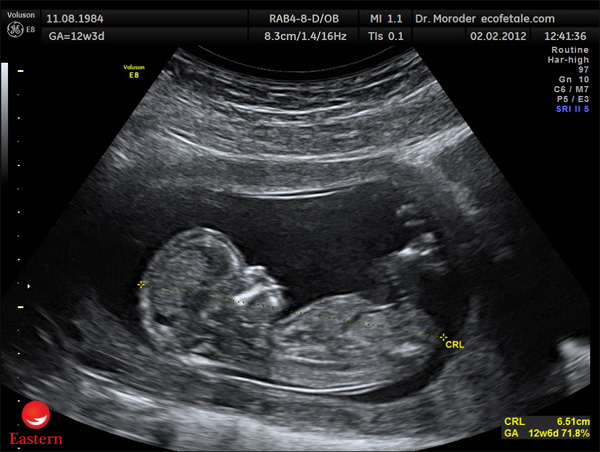

Chỉ số FL trong siêu âm thai đại diện cho chiều dài xương đùi của thai nhi, được đo và ghi lại bằng công nghệ siêu âm. Đoạn xương này đóng vai trò quan trọng trong việc xác định kích thước của thai nhi, giúp các chuyên gia y tế đánh giá sự phát triển của thai kỳ một cách chính xác và chi tiết.

Chỉ số FL cho biết chiều dài xương đùi thai nhi

Trong quá trình siêu âm, bác sĩ sẽ xác định chiều dài xương đùi của thai nhi bằng cách sử dụng đầu dò siêu âm đặt lên bụng mẹ. Đây là một quy trình an toàn, không gây cảm giác đau đớn cho cả mẹ và bé. Sau khi thu thập các số liệu, bác sĩ sẽ ghi nhận kết quả vào báo cáo siêu âm để theo dõi và đánh giá sự phát triển của thai nhi qua các giai đoạn khác nhau.

Siêu âm thai là công nghệ hiện đại, quan trọng và đáng tin cậy trong việc chăm sóc sức khỏe mẹ bầu. Bằng cách sử dụng sóng siêu âm để tạo ra hình ảnh rõ nét về thai nhi và tử cung, bác sĩ có thể theo dõi sự phát triển của thai kỳ một cách chi tiết và chính xác. Trong quá trình này, nhiều chỉ số quan trọng, bao gồm chỉ số FL, cũng được đo đạc và đánh giá.